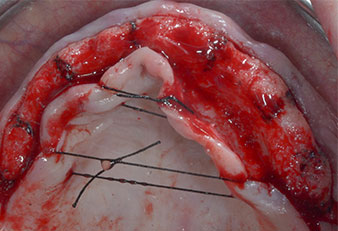

Tre anni dopo era il momento di una protesi dentaria mascellare dello stesso tipo. In base alla pianificazione con CBCT, il rialzo del seno mascellare è stato evitato con l'ausilio di impianti corti e una dima chirurgica è stata utilizzata per trasferire le posizioni pianificate alla cresta alveolare (Figg. 1 e 2).

Uno strumento piezoelettrico (Piezomed I1) a forma di fiamma, rivestito in diamante, è stato usato per contrassegnare le posizioni dell'impianto e per eseguire una preparazione pilota (Fig. 3). Si è prestato attenzione a utilizzare un movimento verticale ascendente e discendente, con potenza ridotta, irrigazione completa e bassa pressione (inferiore a 300 g). Successivamente è stato applicato uno strumento pilota (Piezomed I2A/I2P) per l'ingrandimento iniziale delle sedi dell'impianto del diametro di 2 mm (Fig. 4), seguito da un inserto da 3 mm (Fig. 5).

A causa dell'osso relativamente duro (D2) in quest'area, le sedi dell'impianto di 10 mm nelle posizioni 11 e 21 sono state finalizzate con un trapano rotante da 4 mm di diametro, in combinazione con un contrangolo chirurgico W&H WS-75 L, il motore per impianto W&H Implantmed e il modulo opzionale Osstell ISQ di W&H. Al contrario, a causa dell'osso morbido, le sedi posteriori sono state preparate a un diametro finale di 3 mm utilizzando lo strumento Piezomed I3P. Gli impianti sono stati infine posti per via transgengivale sull'osteointegrato per tre mesi (Figg. 6-10). La protesi dentaria esistente è stata mantenuta su quattro impianti provvisori (Fig. 8).